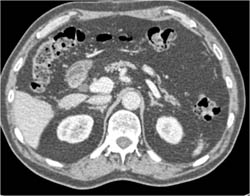

Hemangioma in 3D